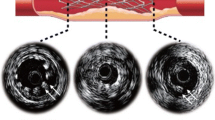

Stent grafts are medical devices used for the treatment of aneurysms; the irreversible dilation of blood vessels by at least 50%. With the use of catheters, these devices are inserted and deployed into large aneurysmal arteries, usually the aorta or the iliacs (Fig. 1). During the last decade, computational models have been developed to support the design of stent grafts, in order to better understand the relation between device geometry and mechanical variables of medical importance (e.g., maximum strain, radial force, fixation force),2,10,14,15,20,21,22 providing insights for both clinicians and stent device manufacturers alike.

The Anaconda™ stent graft placed inside an abdominal aortic aneurysm (AAA).25 The 1st proximal ring bundle is shown in detail illustrating the multiple turns of Nitinol wire sutured onto the fabric.

Herein, ring stent bundles are considered. Such geometries are found in devices like the Anaconda™ (Terumo Aortic, Glasgow, UK) and so far, whenever numerically examined, researchers employ significant simplifications to study them mechanically. The reduction of the number of wire turns,8,23,24 the omission of the manufacturing process8,23,24 and the utilization of double symmetry4,26 are the major modeling techniques followed, all restricting the models’ accuracy or applicability. As a result, to the best of the authors’ knowledge, there is no model currently available in the literature that can capture the mechanical state of a full ring stent bundle accurately, with the versatility to be applied to complex implant geometry simulations.

In the present study, the development and evaluation of a reliable finite element analysis (FEA) model of a full ring bundle consisting of Nitinol wires was pursued. This model did not use symmetry conditions while it did take into account the strains induced in the structure due to the manufacturing process. At the same time, computational expense was kept at a minimum. The FEA model presented constitutes a new approach on ring bundle analysis, since the developed technique allows the reliable simulation of full ring models. This approach can permit the reliable assessment of strains, can enable the deployment in asymmetric and/or patient-specific conditions and can pave the way for efficient full device models. Such abilities can enhance the current understanding of ring stent failures and aid future stent designs in accommodating challenging aneurysmal cases, eventually reducing endoleaking and migration, two of the major causes of post-op endovascular aneurysm repair (EVAR) complications.18,27

Ring stents present in devices such as the Anaconda™ are circular wire bundles sutured to a tubular polyester fabric (Fig. 1). Each one of these bundles is constructed from multiple turns of a single Nitinol wire. The wire is originally straight and is formed into a bundle by being turned multiple times onto a mandrel; then, its two ends are crimped to form a closed ring (Fig. 2a). Because the ring stents act as discrete components, with the fabric accommodating the curves of the artery, it has been deemed appropriate to simplify the complex loading environment the endovascular ring stent device experiences to focus on radial loading of a discrete ring stent. Herein, Abaqus/Standard (version 6.13-2, Dassault Systemes Simulia Corp., RI, USA) has been used to model a ring stent under two case studies, a load–deflection test and a deployment inside a vascular section. The modeling approach followed is presented below.